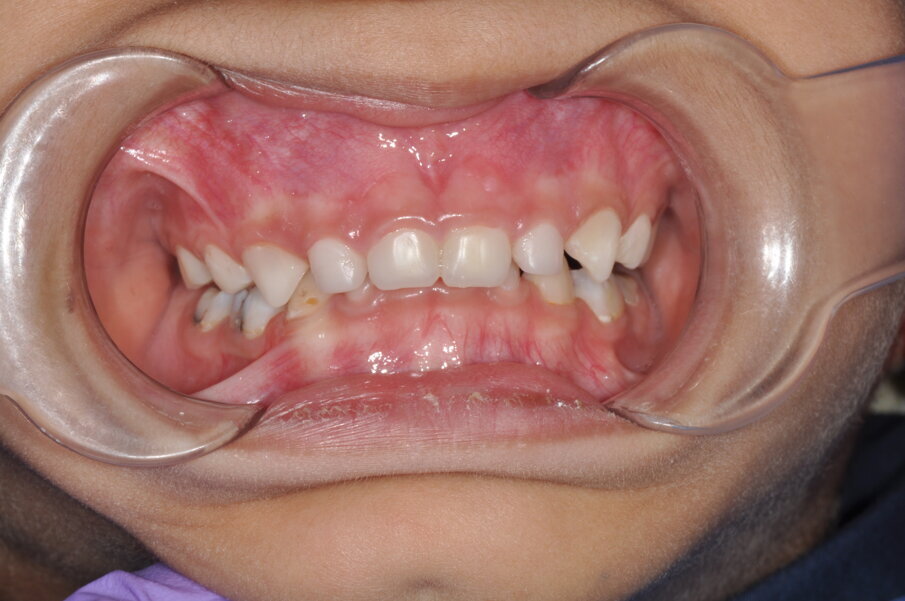

A 4-year-old girl was referred to the Children’s Dental Center in Gurgaon in India with the complaint of painful teeth when eating and the presence of unsightly maxillary anterior teeth. Clinical examination showed large carious lesions in the maxillary anterior teeth (Fig. 1). A radiographic examination showed pulpal involvement of caries in teeth #51 and 61 (Fig. 2).

Fig.1: Caries associated with the four front teeth.